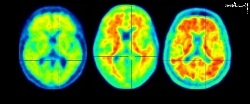

به گزارش «خبرنامه دانشجویان ایران»؛ آلزایمر بیماری است که به آرامی عملکرد مغز بیماران را کاهش می دهد و باعث سردرگمی و مشکلات دیگر می شود. این روش جدید رساندن داروها، کمک می کند تا پلاک های مسدود کننده مغز که باعث این بیماری می شود، حذف شود.

امواج صوتی کوچک ایجاد شده توسط ابزار اولتراسوند منافذی را در آنچه که سد خونی مغزی نامیده می شود ایجاد می کند. سدخونی مغز پوششی محافظ رگ های خونی است که از ورود باکتری ها و سایر مواد مضر به مغز جلوگیری می کند. با این حال، این مانع همچنین از ورود داروهای آلزایمر به مغز جلوگیری می کند. اما این روش جدید به دارو اجازه می دهد تا راحت تر وارد مغز شود و پلاک را سریعتر از بین ببرد.

تاکنون این ابزار تنها بر روی سه بیمار استفاده شده است و در هر بیمار نسبت به درمان سنتی، پلاک سریعتر از بین رفته است. دکتر علی رضایی از موسسه علوم اعصاب راکفلر دانشگاه ویرجینیای غربی که این مطالعه را رهبری کرد، گفت: «هدف ما این است که یک روش جدید را برای بیماران آغاز کنیم. او توضیح داد که برخی از درمان های جدید آلزایمر به زمان زیادی نیاز دارند تا عمل کنند. اما با ابزار اولتراسوند، داروها سریعتر وارد مغز می شوند.

تیم تحقیقاتی به مدت شش ماه هر ماه یک دوز از داروی Aduhelm به سه بیمار داد. بلافاصله پس از هر تزریق، این تیم سونوگرافی متمرکز را در قسمتی از مغز که پلاک ایجاد میکند، هدف گرفت. در نتیجه، مقدار بیشتری از دوز روزانه دارو از سد خونی مغزی عبور کرد.